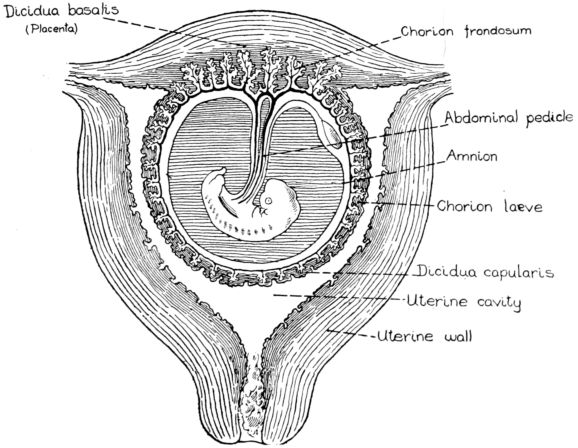

| 20. | Diagram of developing fetus, cord, membranes and placenta in utero | 69 |

| 21. | Diagram of structure of placenta | 71 |